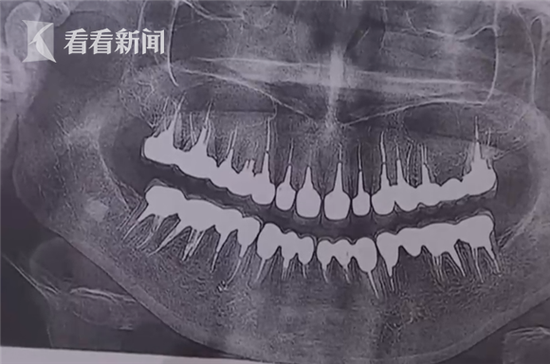

据俄罗斯侦查委员会证实,圣彼得堡伏龙芝区一家私人诊所的医生兼创办人“在牙医服务问题上误导一名患者,拔掉了她的22颗健康牙齿,给她安了质量不过关的假牙”。这名女患者为此支付了84万多卢布,相当于1.5万多美元。